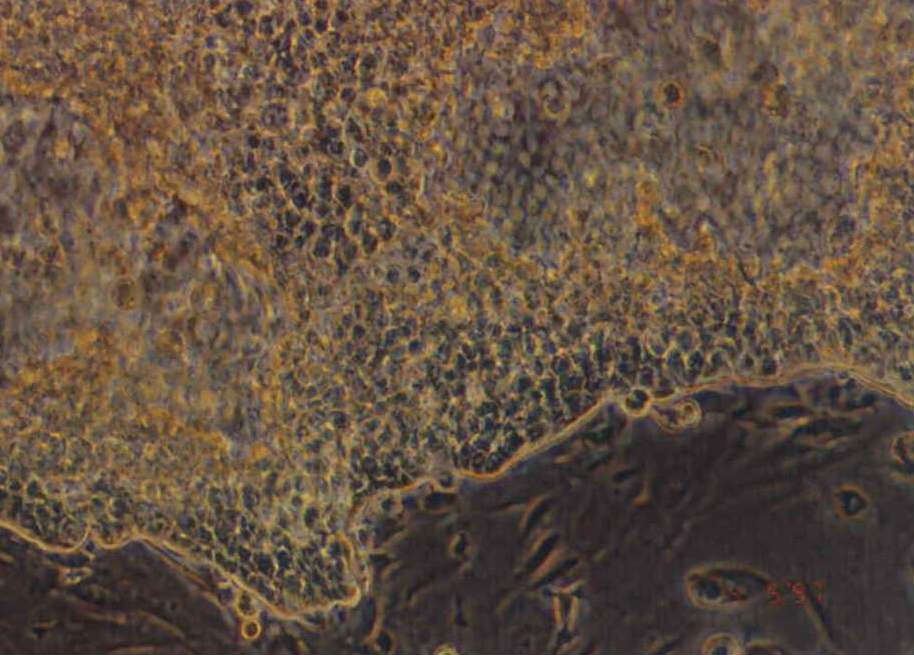

人類基因體解碼後,癌症的基因治療又往前邁進一步。國內從事多年的基因治療研究,已接近進行人體實驗的階段。圖上方是不斷增生的癌細胞,下方則是正常細胞。(中研院生醫所研究員楊文光提供)(中研院生醫所研究員楊文光提供)

基因治療必須藉由載體將基因傳送進細胞中,圖中棕色的細胞顯示基因已傳送進去並開始表現。(中研院生醫所研究員楊文光提供)(中研院生醫所研究員楊文光提供)